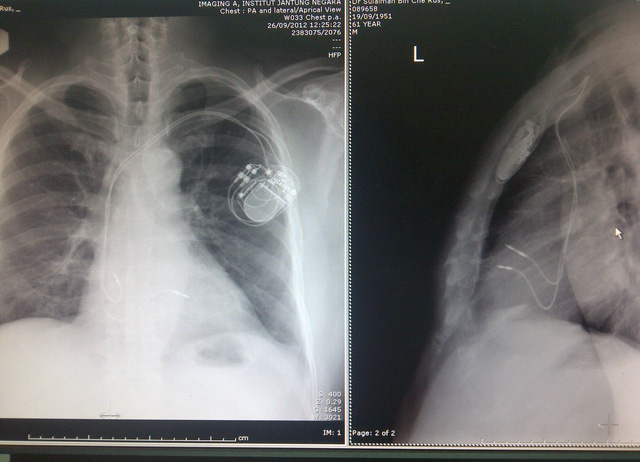

Hình ảnh X quang bệnh nhân sau cấy máy tạo nhịp 2 buồng. Ảnh: BSCC

Máy tạo nhịp tim, hiểu đơn giản là một hệ thống bao gồm máy điều hòa nhịp tim và dây dẫn, có đường kính bằng quả bóng bàn. Sau khi được cấy, máy tạo nhịp chỉ hoạt động khi nhịp tim quá thấp (dưới 50 lần/phút).

Thủ thuật cấy máy tạo nhịp tim thường rất an toàn, đơn giản và không cần phẫu thuật mở tim, chỉ cần rạch da một đường nhỏ khoảng 5-10 cm ở ngay dưới xương đòn bệnh nhân và dẫn dây, đặt máy. Đây là thủ thuật ít đau, đa số chỉ cần gây tê tại chỗ, không cần gây mê nên bệnh nhân vẫn tỉnh táo khi thực hiện thủ thuật (khoảng 30-45 phút).

Chia sẻ với PV sau khi cấy máy tạo nhịp tim 2 buồng, bà H cho biết: Ban đầu, khi nghe bác sĩ tư vấn cấy máy, bà rất ngại và lưỡng lự vì “tự nhiên đeo cái máy trong người”. Nhưng nguy cơ suy tim, đột tử nhỡn tiền, bà đã mạnh dạn cấy máy.